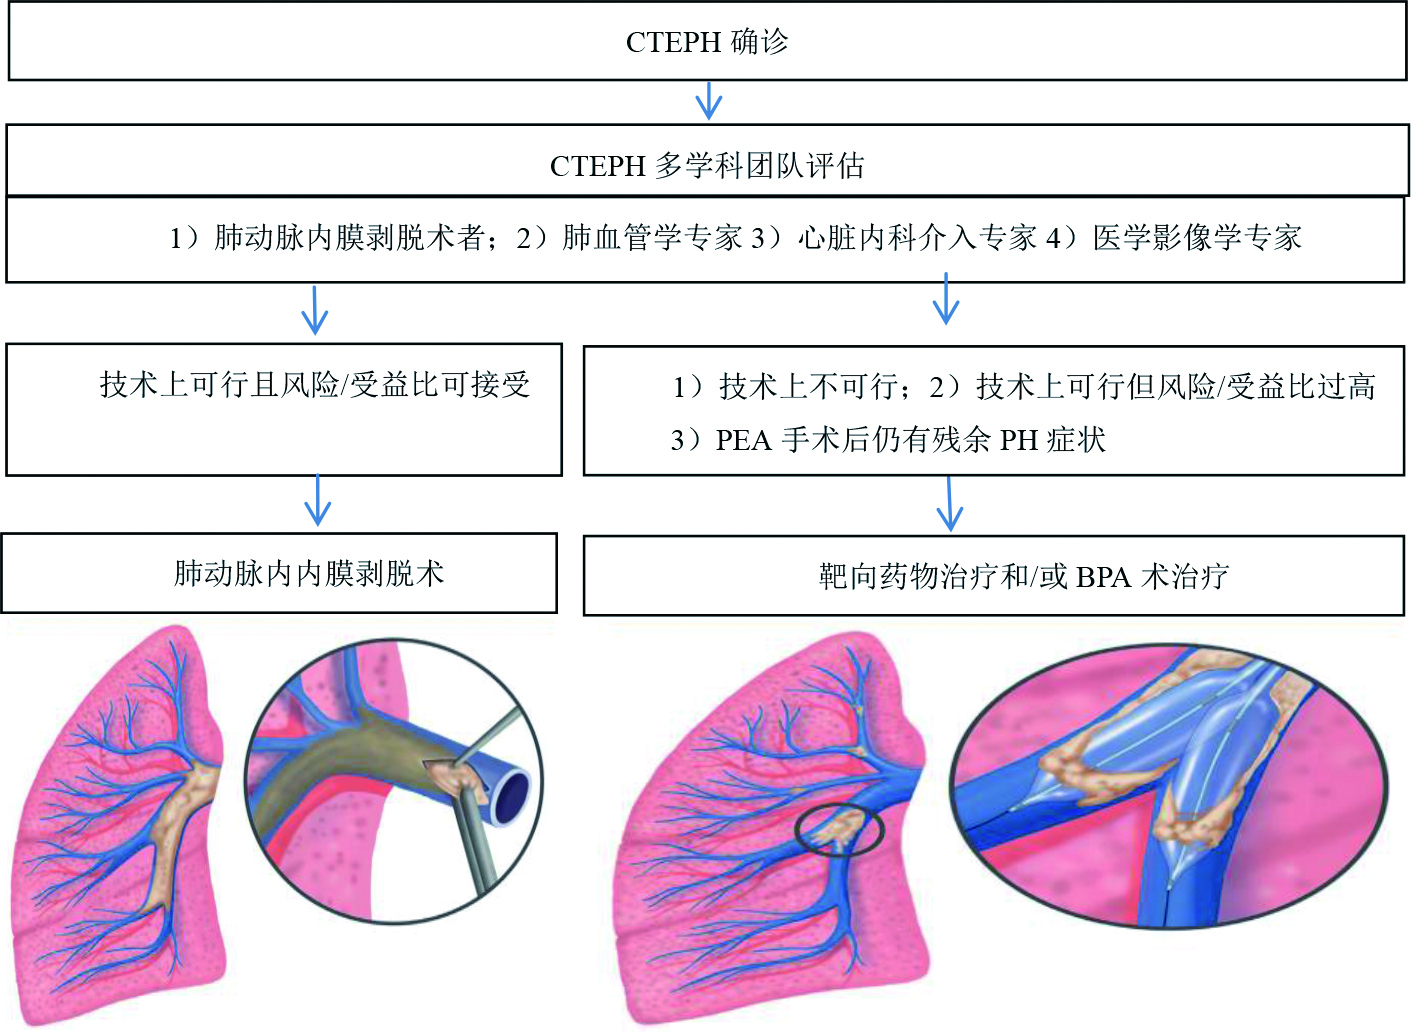

5 CTEPH治疗CTEPH患者无论选择何种治疗方案,均需要终身抗凝[1]。一旦确诊CTEPH,患者需要评估PTE手术(PEA)的可行性。如手术不可行或术后出现持续性肺高压症状或手术风险过高,需要考虑靶向药物治疗或靶向药物联合球囊肺血管成形术(balloon pulmonary angioplasty, BPA)治疗。通常会选择药物治疗联合BPA以稳定血流动力学并改善预后[18]。

5.2 介入治疗鉴于栓塞部位手术难度过大、PVR升高程度与可行手术的栓塞部位程度不匹配、PVR > 15 wood或年龄、并发症等原因无法行手术治疗的患者约占1/3[13],且另有一部分患者即使PEA很成功,但术后仍存在肺高压,此部分患者可尝试进行BPA治疗。所以,不宜行PEA的CTEPH患者可考虑BPA治疗,但由于手术评估的复杂性(需要考虑年龄、肺血管阻力、栓子部位、右室衰竭程度及患者的倾向等[50])及术后肺水肿的发生率较高[51],建议由肺血管学专家、心脏内科介入专家、PEA外科专家及医学影像学专家组成的多学科专家小组CTEPH患者是否适合行BPA术。基于BPA缺乏长期预后的RCT研究,2015年ESC指南对BPA的推荐力度仅为IIb/C[1, 52],也有建议将PEA及BPA联合应用[1, 41]。对于不能行PEA且不宜应用靶向药物治疗的患者是否能真正从BPA中获益尚不完全清楚,仍需进一步研究。

5.3 药物治疗药物治疗适用于不能接受手术治疗、顽固性肺高压及术后复发的患者。但必须强调的是,药物治疗不能作为手术治疗的替代方案(表 3)。药物治疗只适用于非手术适应证CTEPH患者的治疗(图 6)。